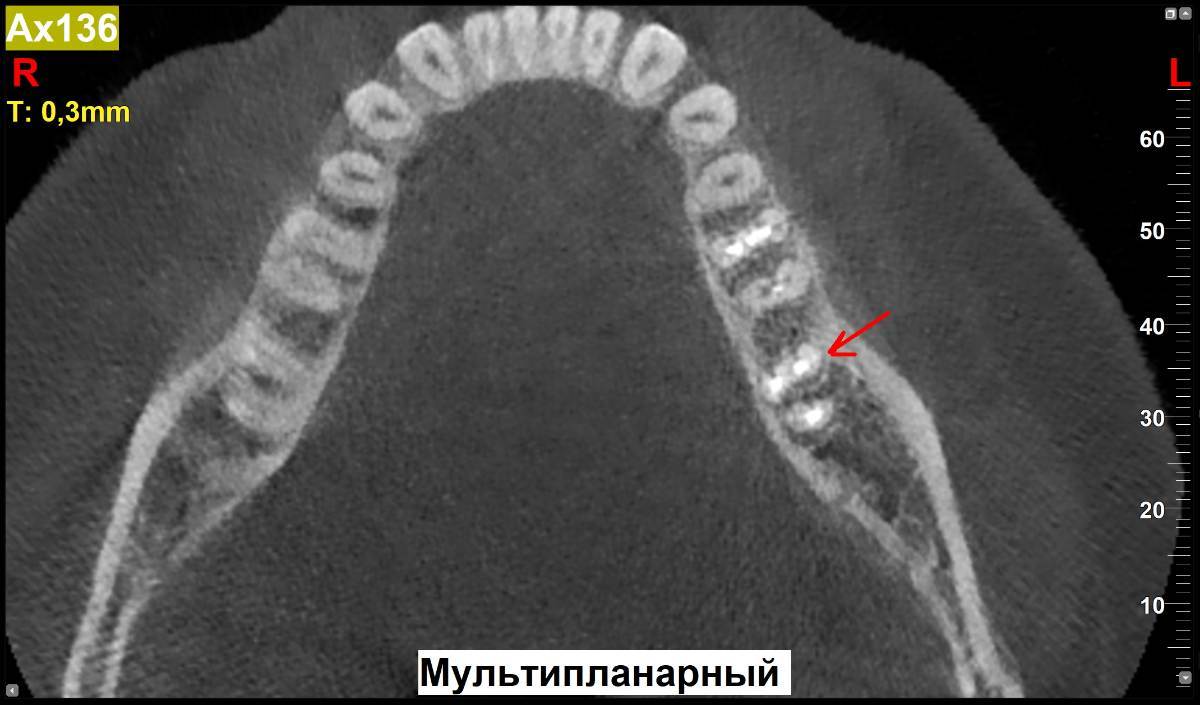

МаксимККК Опубликовано 5 ноября, 2025 Поделиться Опубликовано 5 ноября, 2025 https://disk.yandex.ru/d/6w20ekADUUrt0w Здравствуйте. Установили вкладку на 37 зуб, при снятии слепка под вкладку, ортопед подготовил 2 канала под две ножки вкладки, но с первого раза не получилось снять (ножка сломалась), снял слепок под одну ножку. Вкладку сделали с одной ножкой. Однако, второй канал остался не востребованным и появился вопрос, после сделанного КТ через пару недель после установки вкладки. А запломбировали ли распломбированный канал или он остался просто пустым? И если он остался пустым (ни чем не закрытым), приведет ли это к размножению микроорганизмов в пустоте или другим негативным эффектам? Если оставили пустым, нужно ли снимать вкладку и пломбировать канал? Спасибо. Ссылка на комментарий

МаксимККК Опубликовано 5 ноября, 2025 Автор Поделиться Опубликовано 5 ноября, 2025 1 час назад, Doc сказал: Пустым его оставить не могли, т.к. вкладка сажается на цемент, который закрывает все пустоты. Спасибо за ответ. Сперва подготовили 2 канала, но модель с 2мя ножками под отливку вкладки, не получилась, по этому в этот же прием, во второй раз, сделали на одной. Один канал при установке заполнен ножкой с цементом, а второй уже не понадобился, по этому и спрашиваю, судя по снимкам осталась ли там пустота, после установки (возможно ортопед не отметил в карте, что делал 2 канала и его не запечатал) и если так, чем это чревато. 4 часа назад, red_butler сказал: Здравствуйте, все хорошо, не переживайте. Спасибо за ответ. Ссылка на комментарий